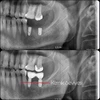

Implant tedavisi